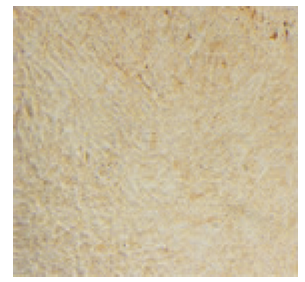

| 图2 肺成纤维细胞的波形蛋白鉴定 |

| Fig.2 Identification of vimentin in pulmonary fibroblasts(×100) |